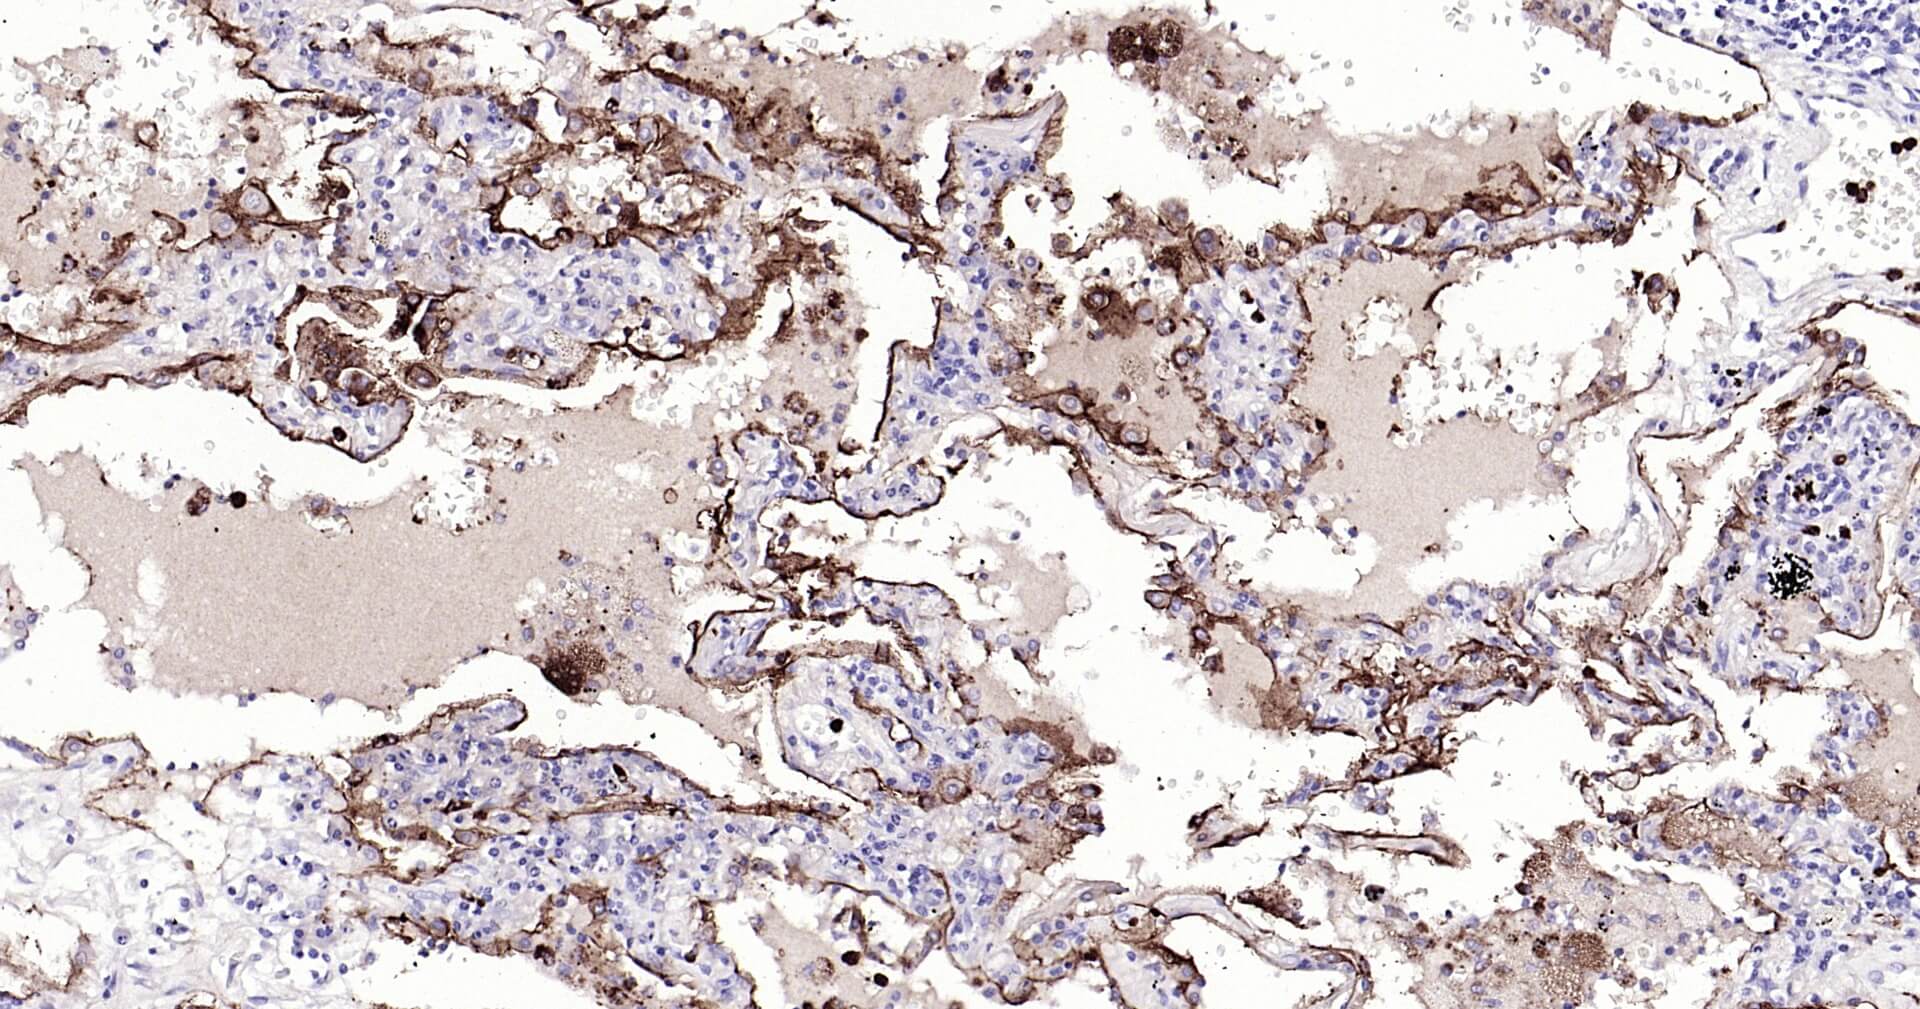

Immunohistochemical analysis of paraffin embedded human lung carcinoma tissue slide using IHC0132H (Human CEACAM5 IHC Kit).